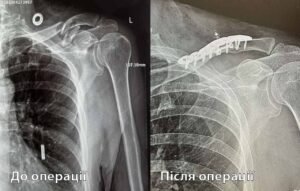

Моя мама потрапила до нього зі складним випадком — перелом в області плеча. Ситуація вимагала високої точності, досвіду та швидких рішень. Операція пройшла швидко та успішно.